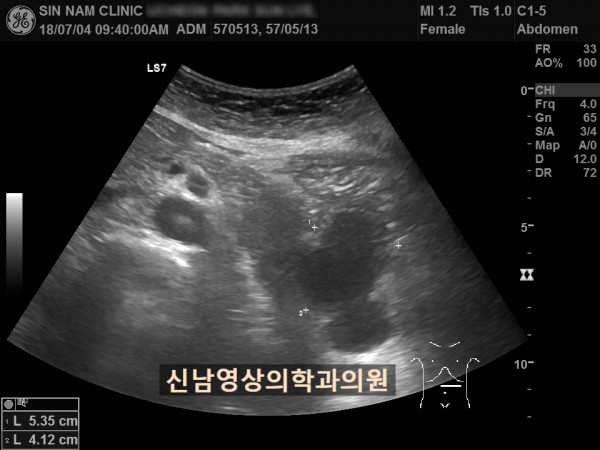

아래 환자분은 60대 여성분으로 식사만 하면 복통이 나타나서 내과에서 위 / 대장 내시경을 받으셨지만 정상으로 진단받았던 분으로 내과에서 복부 초음파검사를 했지만 이상 소견을 발견하지 못했던 분입니다.

복부 초음파 검사상 췌장꼬리(미부)에서 발생한 암으로 대장 장간막으로 전이가 되어서 대장내시경에서는 정상으로 확인되었고, 식사를 하면 장간막 전이때문에 장폐색 증상으로 복통이 발생하셨던 것으로 복막으로 전이가 진행되어 복수까지 있었습니다.